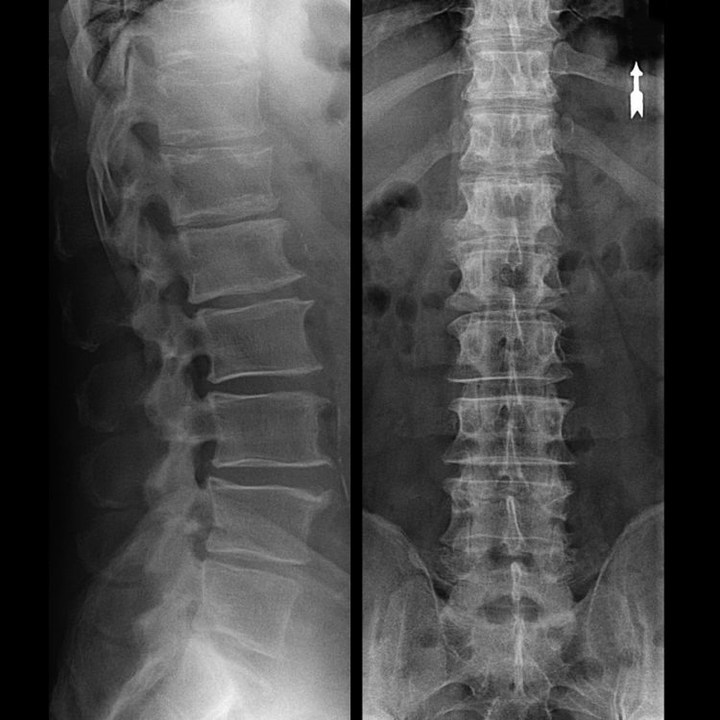

osteochondrosis of the vertebral region on X-ray

In typical cases, as described above, osteochondrosis of the cervical and cervical-thoracic spine occurs.Therefore, the main stage of diagnosis was and remains the determination of the patient's complaints, the presence of muscle spasm accompanied by simple palpation of the muscles along the spine.Is it possible to confirm the diagnosis of osteochondrosis using X-ray examination?

Although there are "x-rays" of the cervical spine and even functional tests for flexion and extension, the cartilage is not visible because their tissue transmits X-rays.Nevertheless, based on the location of the vertebrae, general conclusions can be drawn about the height of the intervertebral discs, the general correction of the physiological curvature of the neck - lordosis, as well as the presence of marginal growths in the vertebrae with long-term irritation of fragile and dehydrated intervertebral surfaces.Functional tests can confirm the diagnosis of cervical spine instability.

Since the discs themselves can only be seen using CT or MRI, magnetic resonance and X-ray computed tomography are indicated to clarify the internal structure of cartilage and formations such as protrusions and tears.Thus, with the help of these methods, an accurate diagnosis is made, and the result of the tomography becomes an indication and even an actual guide for the surgical treatment of hernias in the neurosurgery department.